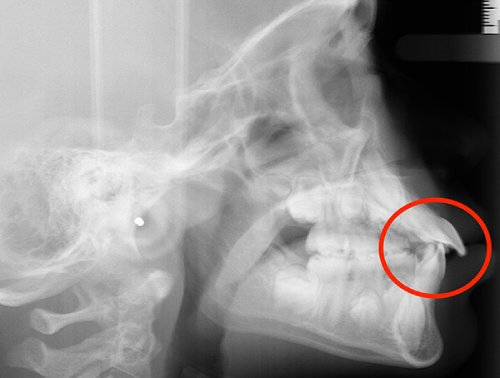

Actual Patient: Alexander

Alexander Before 4 Alexander After 4

Severe “Underbite”, Narrow Jaws, Adult Teeth Not Growing In

Alexander Before 1 Alexander After 1

Front View

Top View

Right & Left Sides